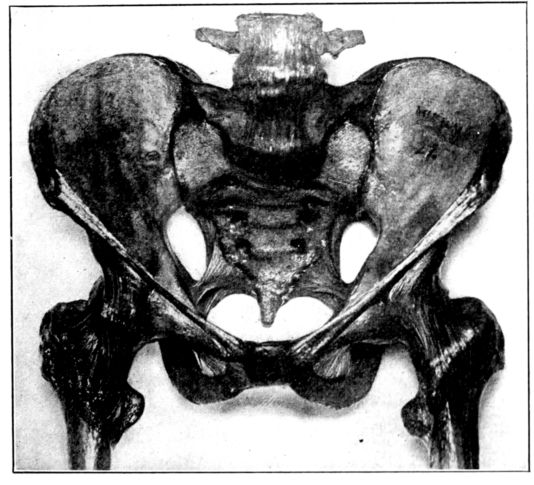

Viewed in its entirety, the pelvis is an irregularly constructed, two-storied, bony cavity, or canal, situated below and supporting the movable parts of the spinal column, and resting upon the femora or thigh bones. (Fig. 1, A. and B.).

A. Normal female Pelvis.

B. Normal male Pelvis.

Fig. 1.—Normal Pelves. Note the broad, shallow, light construction of the female pelvis, A, as compared with the more massive male pelvis, B.

The normal male pelvis is deep, narrow, rough and massive as compared with the female structure (see Fig. 1.), and the angle of the pubic arch, formed by the two pubic bones, is deeper and more acute in the male than in the female skeleton.

The normal female pelvis, on the other hand, is light, broad, shallow, smooth and large, giving evidence of the infinite wisdom and skill that entered into constructing it for the high purpose it was designed to serve.